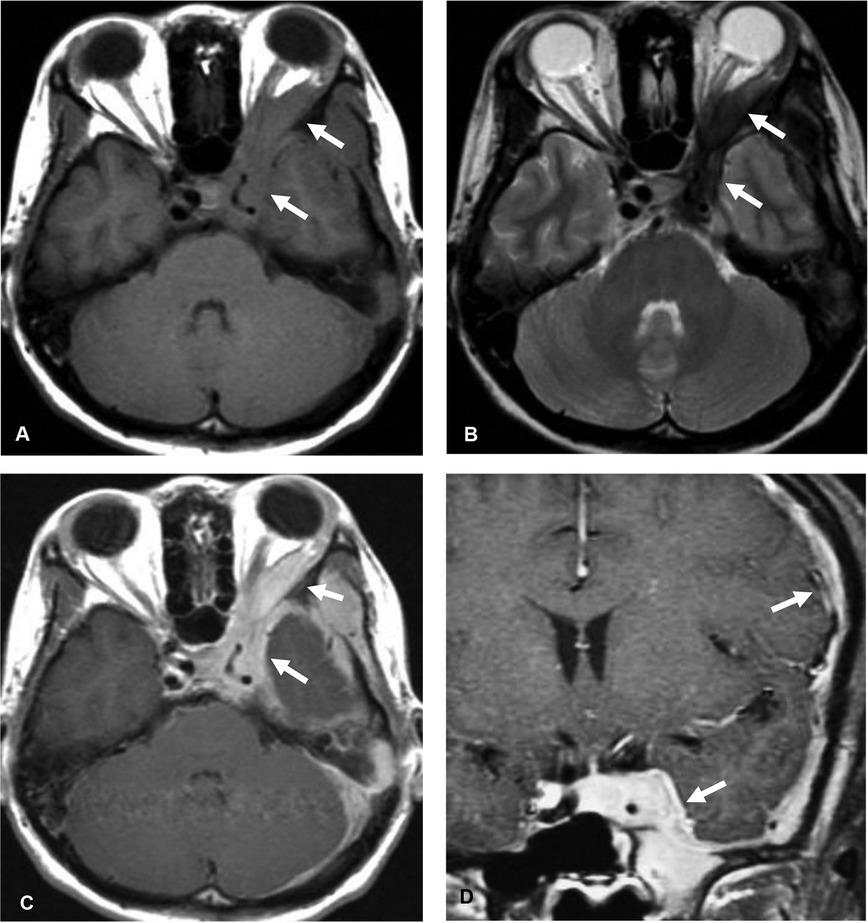

Figure 1

Idiopathic hypertrophic pachymeningitis (IHP). Axial T1-weighted image (A), axial T2-weighted image (B) shows an infiltrative T1 iso-intense, T2 hypointense lesion (arrow) involving left cavernous sinus with extension through left superior orbital fissure to left orbit, along left sphenoid ridge, left middle and posterior cranial fossae. Homogeneous enhancement is shown in axial (C) and coronal (D) gadolinium-enhanced T1-weighted images.